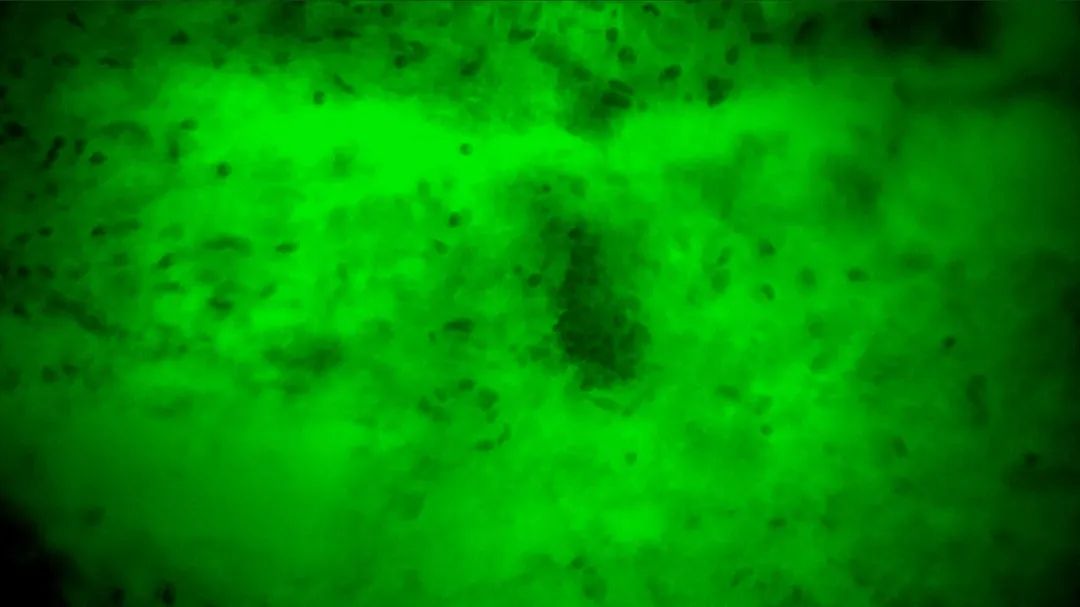

3次切緣掃查的EndoSCell?細(xì)胞圖像

1

陽(yáng)性,細(xì)胞核異型、密集、分布不均勻